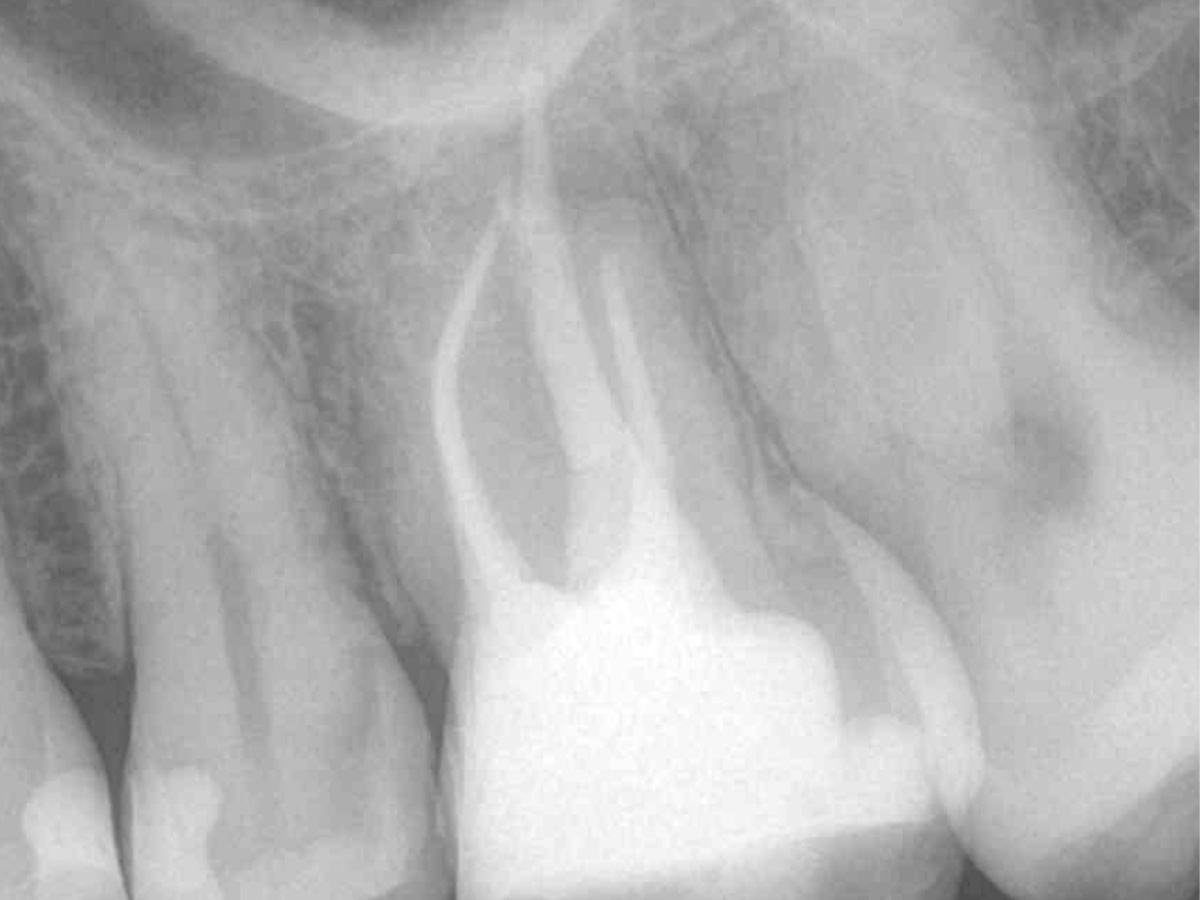

Der Patient stellte sich mit Aufbissschmerzen vor, wobei die klinische und röntgenologische Untersuchung eine symptomatische apikale Parodontitis an einem bereits wurzelkanalbehandelten Zahn 26 ergab. Die DVT-Aufnahme deutete auf einen unbehandelten zusätzlichen Kanal in der mesio-bukkalen Wurzel hin. Die Darstellung und Behandlung des mb2s sowie die Revision der bereits behandelten Kanäle erfolgte mit dem XP-endo® Rise Shaper bei einer hohen Umdrehungszahl von 2.500rpm.

Abbildung 2

DVT koronal